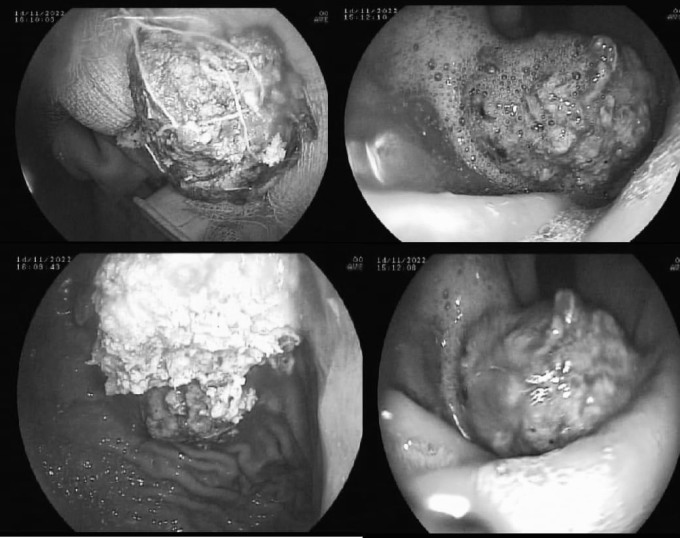

Trước đó, bà mua một kg hồng giòn về nhà ăn, bị đau tức vùng thượng vị, đầy, nóng bụng, nhập viện cấp cứu. Ngày 16/11, bác sĩ Vương Khả Vinh, Phó trưởng khoa Chẩn đoán hình ảnh, Bệnh viện Đa khoa Khu vực Tây Bắc, cho biết ảnh chụp X-quang cho thấy bệnh nhân có khối bã thức ăn kích thước lớn trong dạ dày, màu trắng ngà, gây viêm xuất huyết niêm mạc dạ dày.

Bác sĩ nội soi cắt khối bã thành nhiều miếng nhỏ, sau đó đưa ra ngoài thông qua đường miệng. Sau hơn một giờ, toàn bộ khối bã mới được lấy ra ngoài. Bệnh nhân hồi phục sức khỏe, ăn uống bình thường.

Khối bã rắn chắc trong dạ dày bệnh nhân. Ảnh: Bệnh viện cung cấp